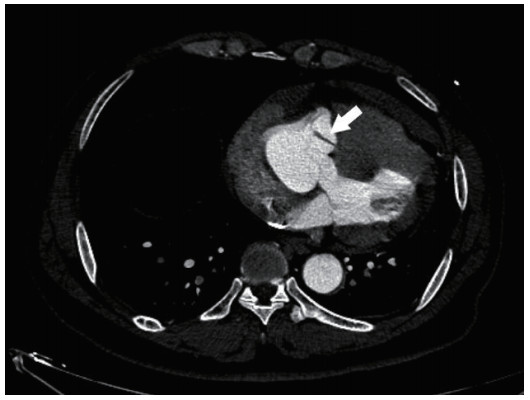

| 图 2 主动脉CTA横断面见主动脉撕裂瓣膜(箭头所示) |